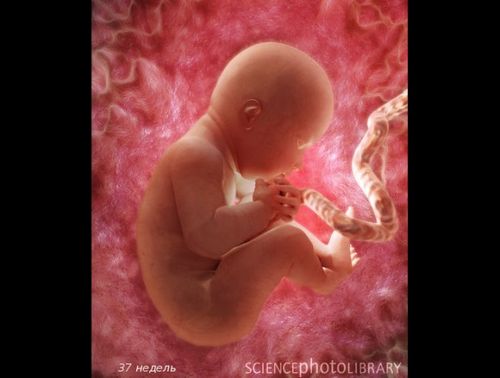

Вагітність по тижнях як виглядає дитина

Вага дитинки складає в середньому 2,500 кг. Довжина малюка - 47 см.

З цього часу плід вважається зрілим і готовий до народження. Він з нетерпінням чекаємо зустрічі з вами!